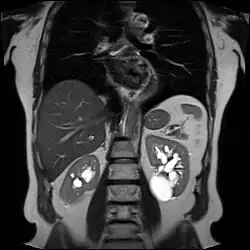

Advanced polycystic kidney disease with multiple cysts.[13] -